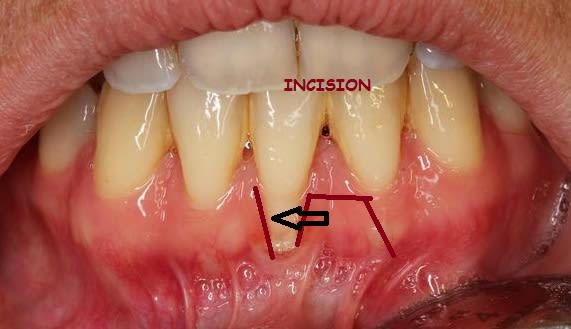

quel serait votre attitude thérapeutique sur une telle récession gingivale,avec brides et parodonte très fin.

Il semble que les papilles soient larges donc lambeau bipapillaire why not ? Voir meme un lambeau déplacé latéralement en prenant la zone sect 3.

Sinon une GEC classique mais faudra aller assez pas dans la dissection et tu en profiterais pour sectionner toutes les fibres en éventail du frein.

Tu n'as pas de GA en apical de ta recession. Mobiliser lateralement les tissus gingivaux environnant t'oblige á faire du mutipapillaire.

Pour faire plus simple, je te conseille de faire une GGL en prenant soin de preparer correctement et suffisament ton lit receveur ( comme on a vu lors de la formation a laquelle tu avais assisté). Greffon adapté et sutures réflechies sont autant de facteurs qui te permettront a mon avis de recouvrir l'ensemble de la retraction sans deuxième intervention.

Tres simple: la gencive attachée disponible pour recouvrir une retraction provient soit en apical de la recession (auquel cas une lambeau déplacé coronairement est indiqué) soit en mesial et/ou distal de la recession ( auquel un lambeau lateralisé est indiqué). S'il n'y en a ni en apical ni en lateral la GGL est le dernier recours.

Oui il y en a Tillc mais la technique bipapillaire pour des retractions au niveau d'incisives inférieures n'est pas aussi smple qu'au niveau d'une canine maxillaire !

Pour cette raison j'ai écrit "Mobiliser lateralement les tissus gingivaux environnant t'oblige á faire du multipapillaire"

Aussi il y a d'autres techniques plus facilement réalisables, moins complexes surtout quand on débute en muco. D'où mon commentaire : "Pour faire plus simple, je te conseille de faire une GGL"

Ensuite tout a fait d'accord avec toi, si on manie facilement le bistouri et se sent a l'aise en muco, si on veut eviter un effet rustine, le lambeau deplacé (bi)lateralement est parfaitement envisageable.